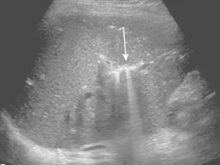

ascites (fluid collection)